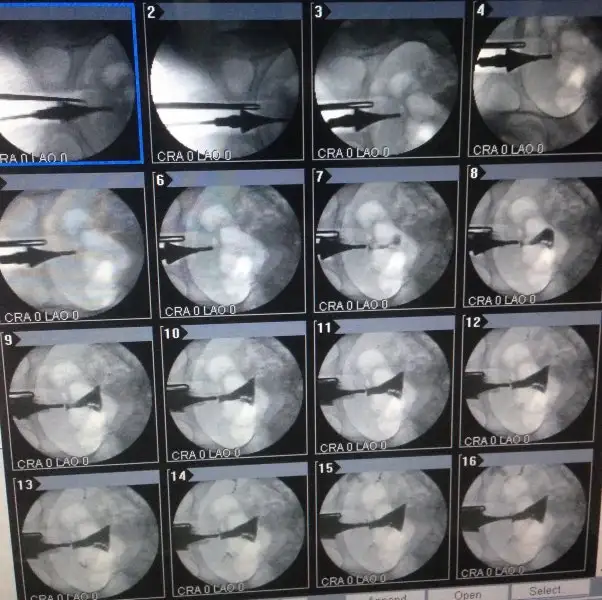

Evet canım görünüyor seninkinde o kabarcık demek ondan öyle. Bide canım bilmediğim için soruyorum senin sol yumurtalık gözükmüyor sanki. Düzgün çekilmemiş mi film

18 olabilir cnm kaç günde bir regl oluyordumMrb canim tabloma bakabilirmisin